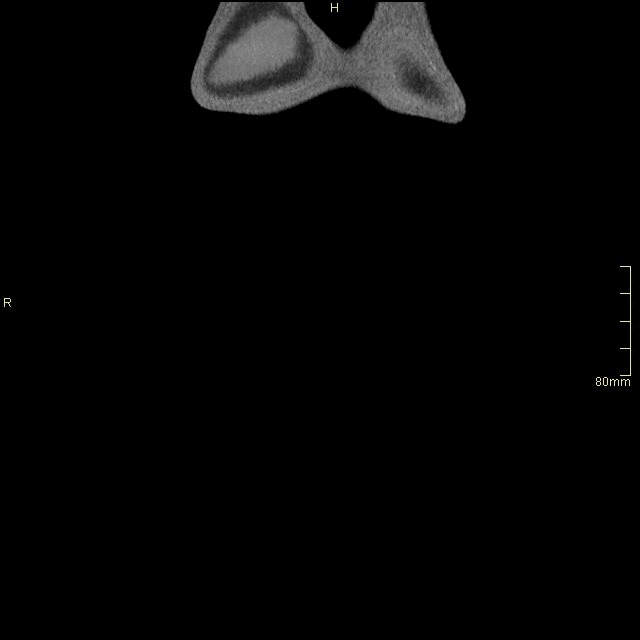

Abdomen Angiogram (Coronal)